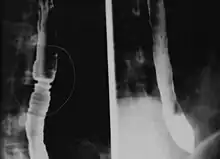

Radiologically, the term "ringed esophagus" has been used for the appearance of eosinophilic esophagitis on barium swallow studies to contrast with the appearance of transient transverse folds sometimes seen with esophageal reflux (termed "feline esophagus").[12]

Endoscopically, ridges, furrows, or rings may be seen in the esophageal wall. Sometimes, multiple rings may occur in the esophagus, leading to the term "corrugated esophagus" or "feline esophagus" due to the similarity of the rings to the cat esophagus. The presence of white exudates in the esophagus also suggests the diagnosis.[13] On biopsy taken at the time of endoscopy, numerous eosinophils can be seen in the superficial epithelium. A minimum of 15 eosinophils per high-power field are required to make the diagnosis. Eosinophilic inflammation is not limited to the esophagus alone and does extend through the whole gastrointestinal tract. Profoundly degranulated eosinophils may also be present, as may micro-abscesses and an expansion of the basal layer.[3][10]